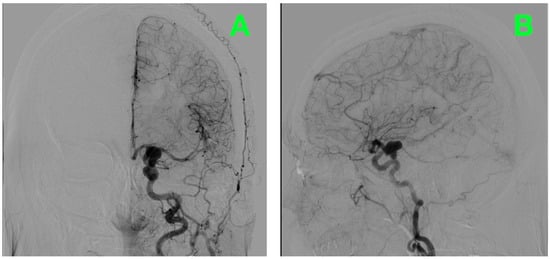

2.9. Closure and Postoperative Verification

2.10. Outcome and Follow-Up